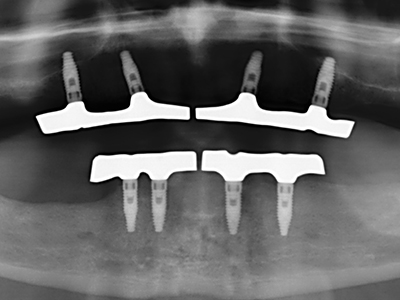

Piezosurgery has additional advantages when harvesting bone blocks. In addition to the high precision with osteotomy described above, the use of the thin saw tips specifically minimizes loss of material. Greater loss of material during harvesting can be expected with the thicker instrument tips, particularly when using Lindemann drills (Lakshmiganthan, Gokulanathan et al. 2012). The basal separation, which is necessary particularly for retromolar block transplants, is simplified by specially designed rectangular saws, with the result that piezosurgery is viewed as a precise, simple and safe procedure for harvesting retromolar bone blocks (Happe 2007) (Fig. 1-12).